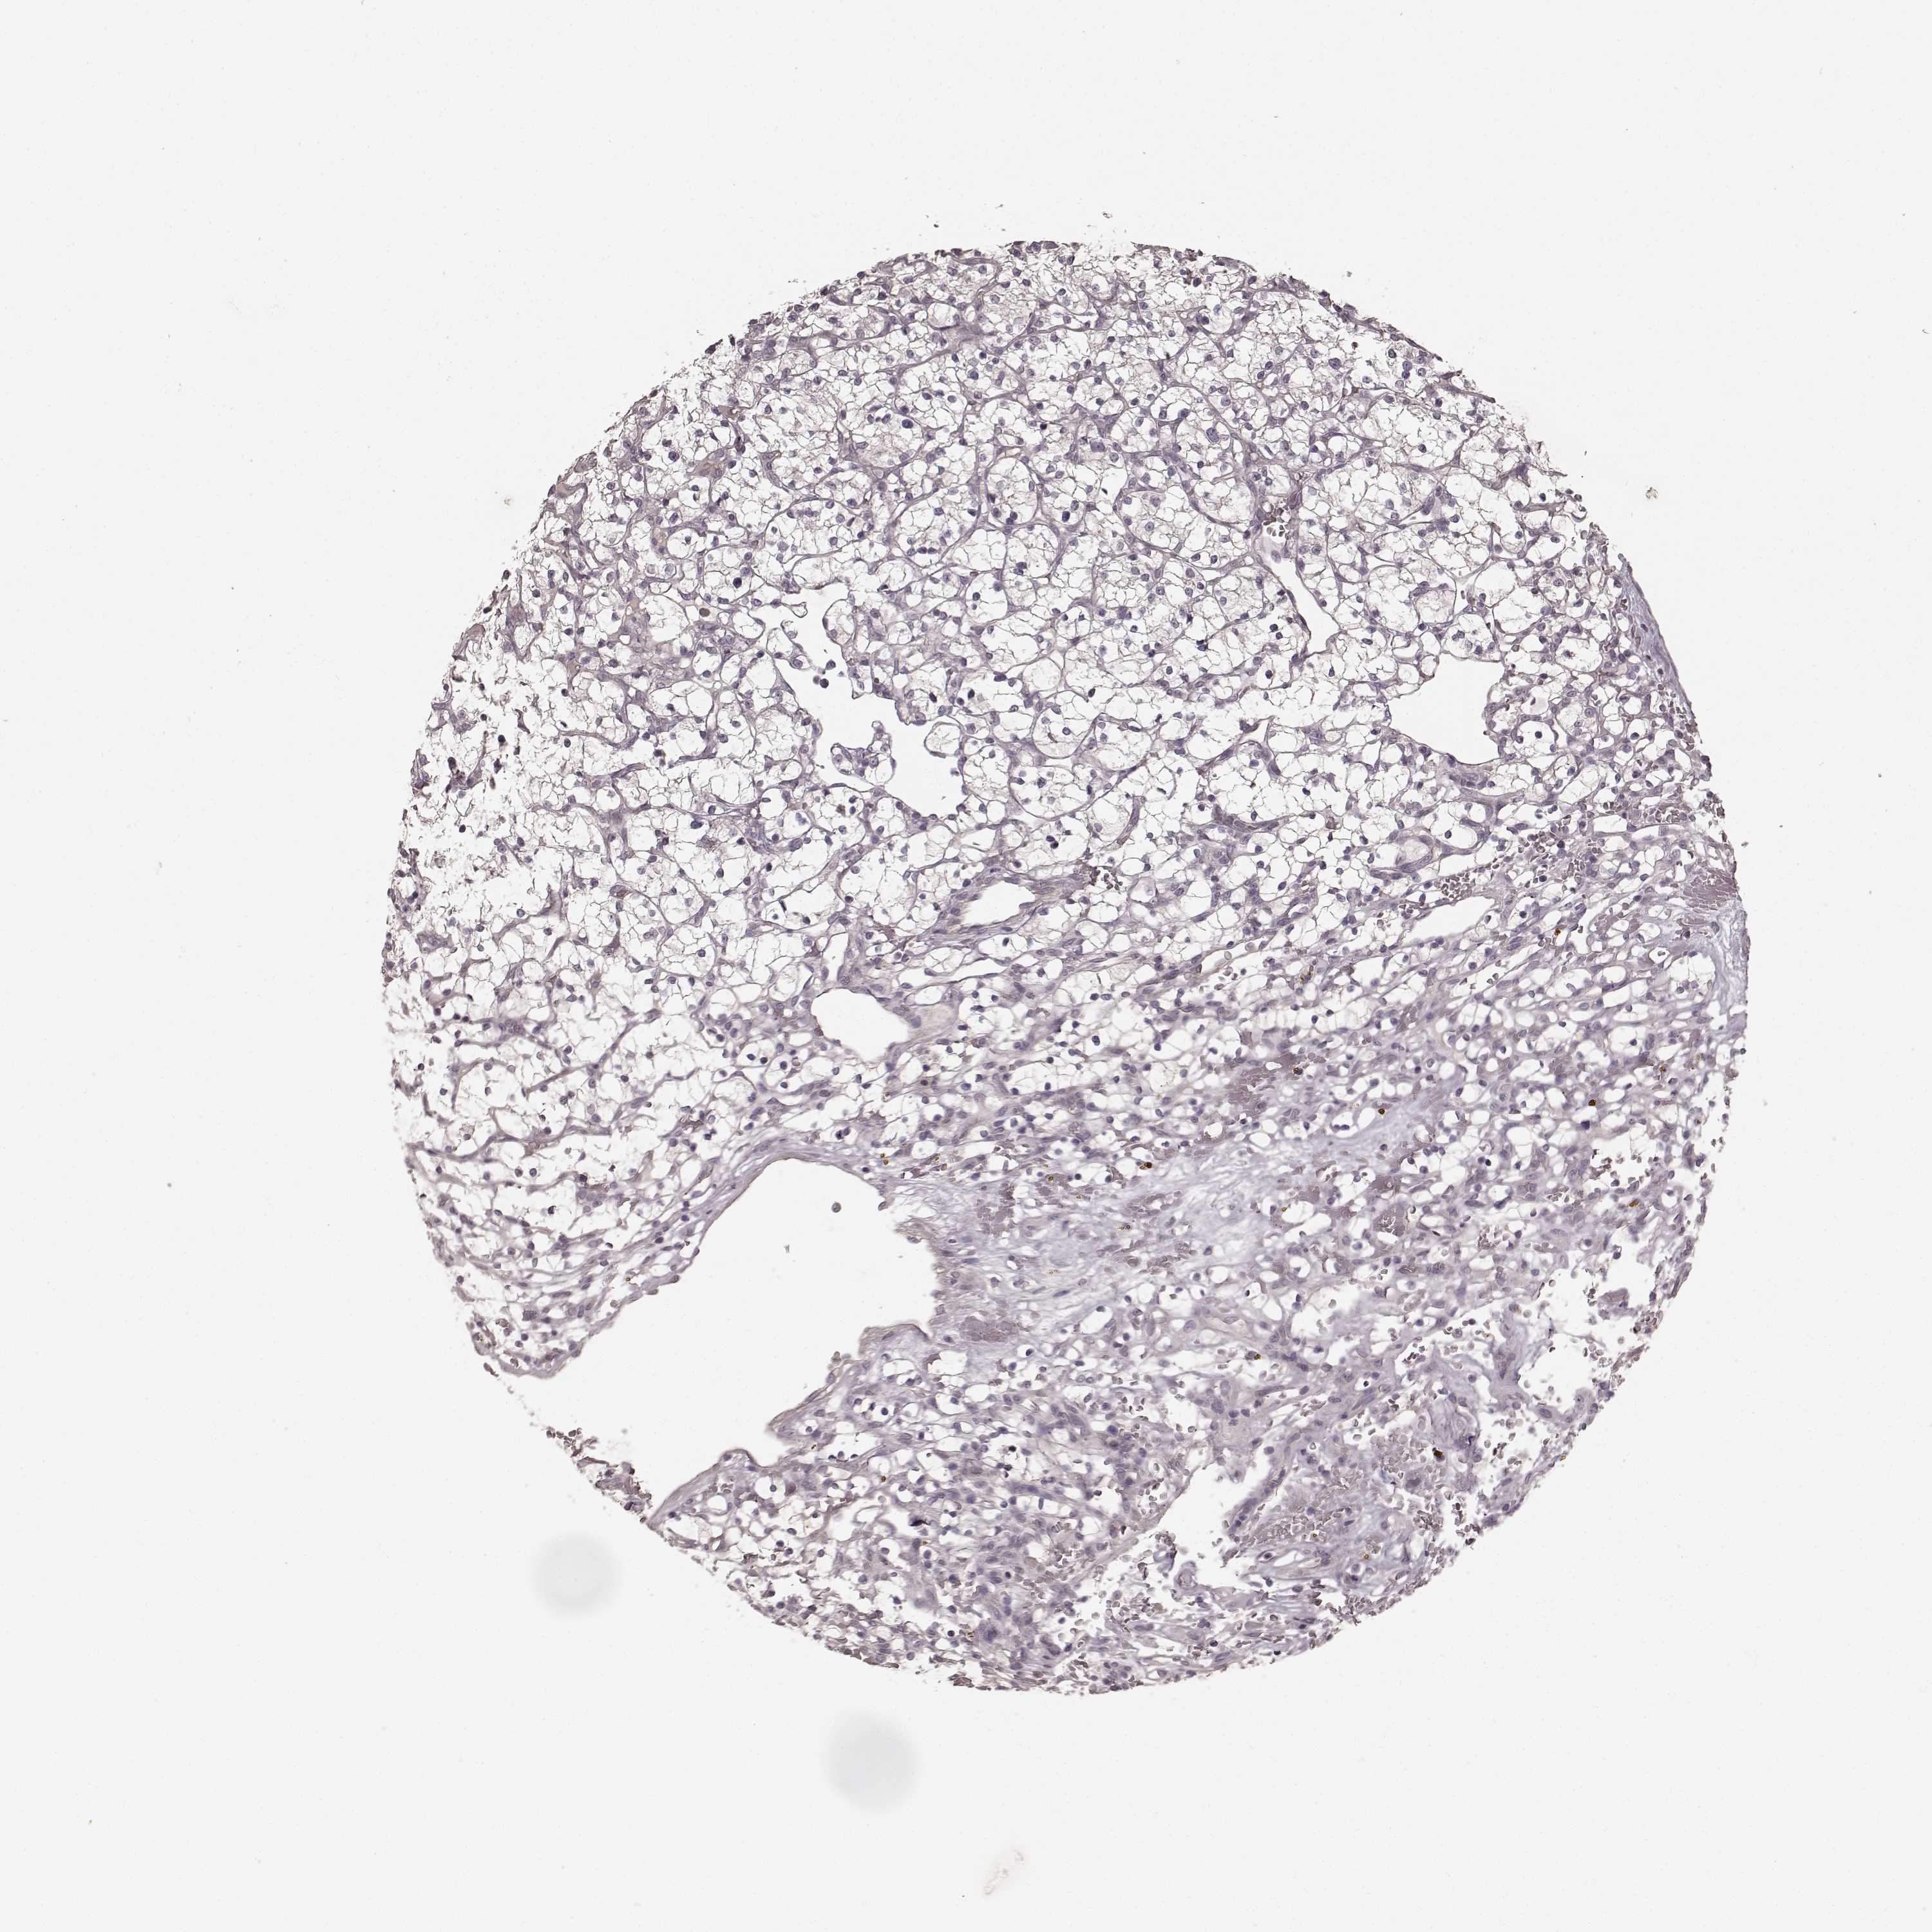

KIDNEY RENAL CLEAR CELL CARCINOMA (TCGA) - Interactive survival scatter ploti

The Survival Scatter plot shows the clinical status (i.e. dead or alive) for all individuals in the patient cohort, based on the same data that underlies the corresponding Kaplan-Meier plots. Patients that are alive at last time for follow-up are shown in blue and patients who have died during the study are shown in red.

The x-axis shows the expression levels (FPKM) of the investigated gene in the tumor tissue at the time of diagnosis. The y-axis shows the follow-up time after diagnosis (years). Both axes are complimented with kernel density curves demonstrating the data density over the axes. The top density plot shows the expression levels (FPKM) distribution among dead (red) and alive patients (blue). The right density plot shows the data density of the survived years of dead patients with high and low expression levels respectively, stratified using the cutoff indicated by the vertical dashed line through the Survival Scatter plot. This cutoff is automatically defined based on the FPKM cutoff that minimizes the p-score. The cutoff can be changed by dragging the vertical line or by entering a cutoff value in the square labeled "Current cut-off".

Under the Survival Scatter plot the p-score landscape (black curve; left axis) is shown together with dead median separation (red curve; right axis). Dead median separation is the difference in median mRNA expression between patients who have died with high and low expression, respectively. It is calculated as follows: median FPKM expression of dead patients with high expression - median FPKM expression of dead patients with low expression. This is intended to aid the user in visually exploring custom cutoffs and the associated p-scores and dead median separation.

Individual patient data is displayed and can be filtered by clicking on one or more of the category buttons on the top of the page. Categories describing expression level and patient information include: high, low, alive, dead, female, male and tumor stages. The scale of the x-axis can be toggled between linear and log-scale by clicking on the "x log" button. Mouse-over function shows TCGA ID, patient information and mRNA expression (FPKM) for each patient.

& Survival analysisi

Kaplan-Meier plots summarize results from analysis of correlation between mRNA expression level and patient survival. Patients were divided based on level of expression into one of the two groups "low" (under cut off) or "high" (over cut off). X-axis shows time for survival (years) and y-axis shows the probability of survival, where 1.0 corresponds to 100 percent.

PRKCE is potential prognostic, high expression is favorable in Kidney Renal Clear Cell Carcinoma (TCGA)

Best expression cut offi

: 4.2

Average pTPM 5.3

Number of samples 521